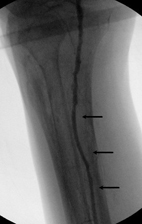

我們用很細的導線,艱困的挖出了其中一條血管(如三個箭頭所指),輔以氣球擴張術,可以看到血液終於下到足部了!雖然患者血液供應仍然不足,但足夠傷口癒合,使患者免除截肢的命運!